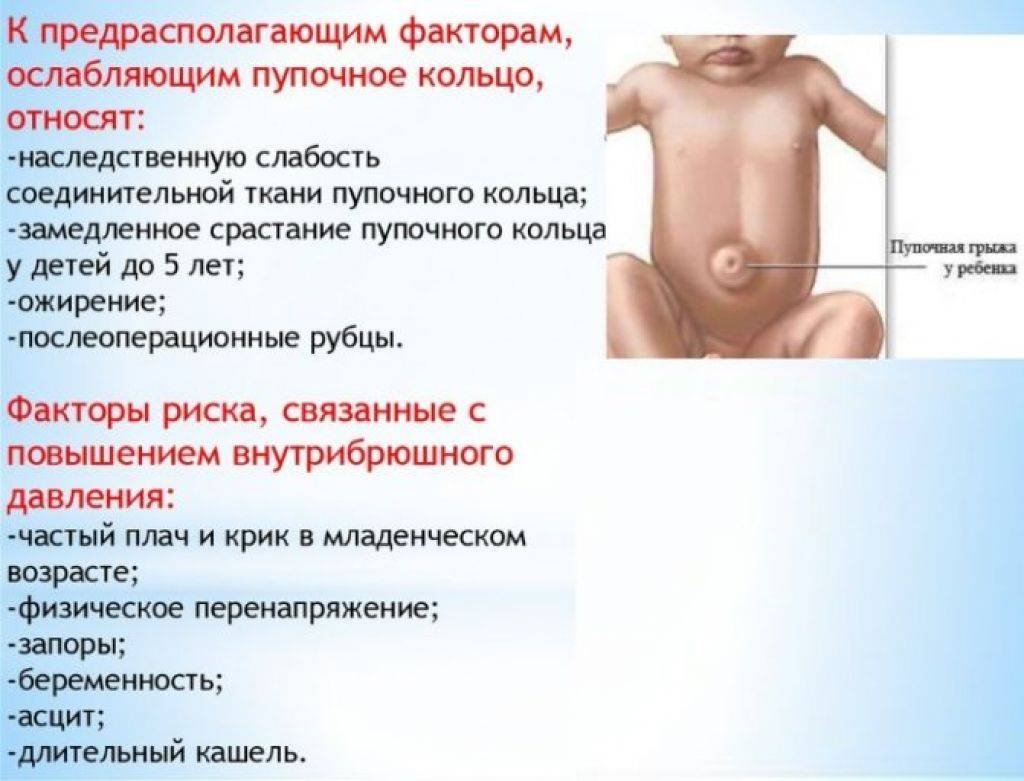

Чаще всего грыжа возникает вследствие дефекта передней брюшной стенки, слабости пупочного кольца. Провоцирующим моментом является длительное повышение внутрибрюшного давления в результате сильного кашля, запоров, продолжительного плача. Такие заболевания, как рахит, гипотрофия, снижающие тонус мышц, создают благоприятные условия для образования пупочной грыжи. Наиболее часто грыжа встречается у недоношенных детей. В пупочную грыжу обычно выпадают петли кишечника ребенка или сальника.

Образование врожденной грыжи. Как уже было сказано, поводом для образования грыжи является ослабление брюшной стенки. И существуют определенные причины, по которым ее формирование в утробе матери происходит не так, как это необходимо. А главной причиной слабости брюшины становится недостаточная прочность мышечной структуры и соединительных тканей — поэтому брюшина начинает развиваться с дефектами. В результате грыжевое образование возникает еще до рождения ребенка, ведь в утробе матери внутренние органы уже начинают оказывать давление на место соединения с пуповинным канатиком.

Чтобы грыже выйти наружу, необходимы определенные условия, главное из которых — сильное давление изнутри, из области брюшной полости. Образуется это давление в некоторых ситуациях:

- если ребенок очень сильно кричит;

- когда малыш сильно тужится при запоре;

- когда ребенок надрывно кашляет;

- при коликах и повышенном газообразовании, вздутии живота.

При дополнительных факторах риска (к примеру, брюшная стенка ослаблена, пупочное кольцо недостаточно крепкое, пупок долго зарастает изнутри) часть органов выпадает из брюшины, и возникает грыжевое образование. Кстати, неграмотные действия родителей тоже могут стать причиной образования грыжи — особенно, если маме или папе не терпится поскорее посадить или поставить ребенка вертикально, помещая в прыгунки или ходунки, а его организм к этому еще не готов. В таком случае при резком увеличении давления на брюшную полость появляется грыжевое образование. Поэтому не стоит торопить события и ускорять природные процессы до того, как малыш достигнет 9-месячного возраста. Пусть ребенок развивается постепенно и поступенчато: сначала он начнет самостоятельно сидеть, затем — ползать и только потом встанет на ноги. Предварительные стадии существуют не просто так — они задуманы природой для укрепления брюшных мышц, которые готовятся к тому, чтобы спокойно выдержать давление внутренних органов без образования грыжи.